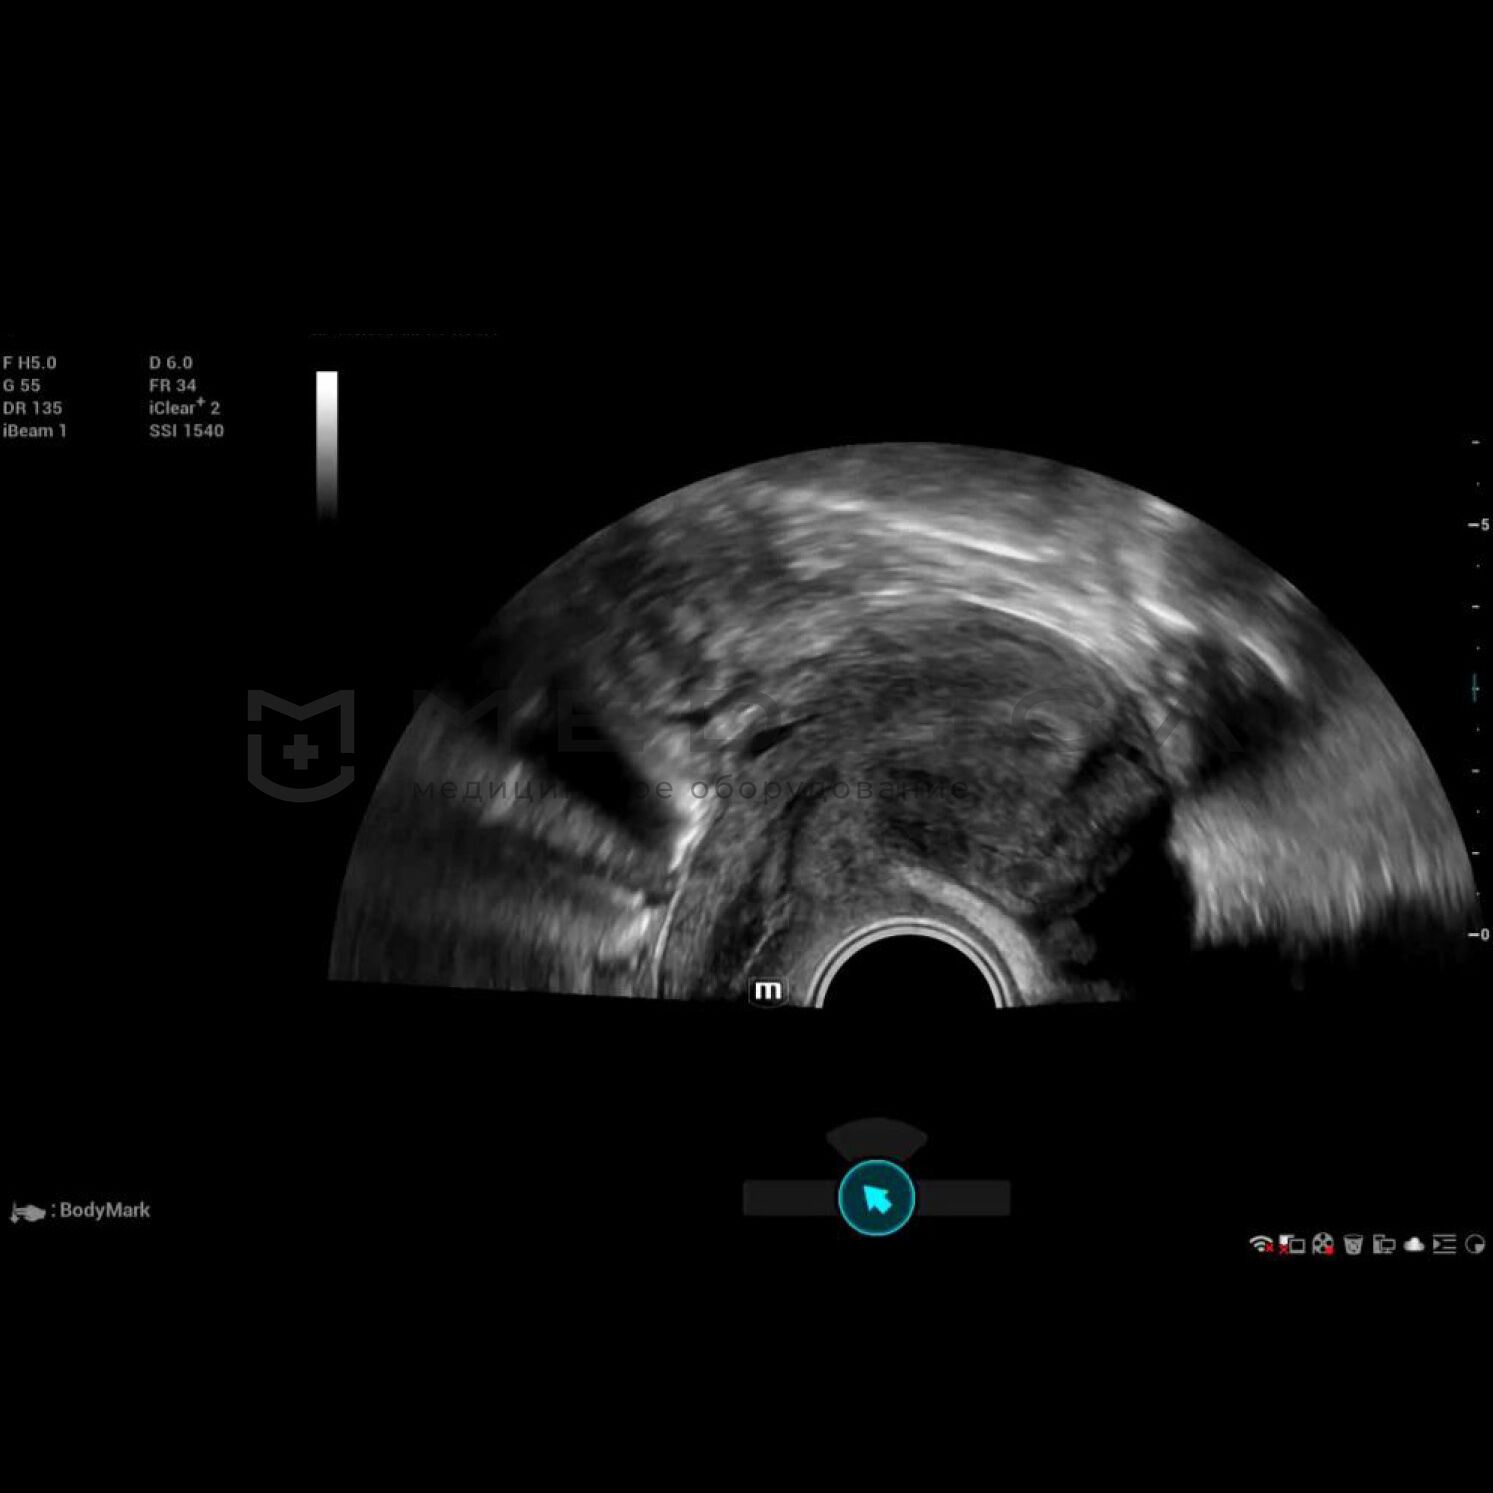

Полноценное интеллектуальное решение для диагностики матки, для легкой и быстрой оценки эндометрия

- Автоматическое распознавание матки

- Автоматическая подстройка зоны интереса и положения до оптимального

- Автоматический объемный рендеринг эндометрия